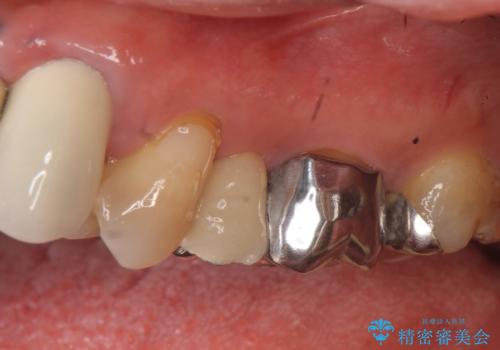

- 昔治療した左上56の延長ブリッジをきちんと治療しなおしたいといらっしゃった方の症例です。

古いブリッジを除去後、オールセラミッククラウンによる補綴を行いました。